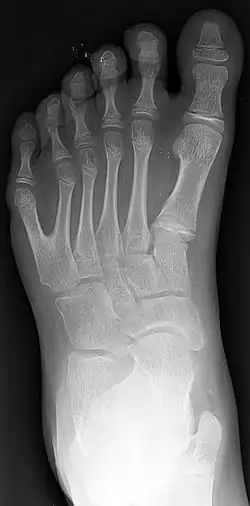

![]() Radiografía de una mano derecha con duplicación de uno de sus dedos | ||

La polidactilia (del griego poly, ‘muchos’ y daktylos, ‘dedo’) es un trastorno genético donde un humano nace con más dedos en la mano o en el pie de los que le corresponde (normalmente un dedo más). Se detecta en el momento del nacimiento. A estos dedos se les llama «dedos extra» o «dedos supernumerarios».

El dedo adicional es generalmente un pequeño pedazo de tejido fino y suave. A veces contiene el hueso sin articulaciones; ocasionalmente el dedo se encuentra completo y funcional. El dedo extra suele ubicarse tras el meñique de la mano o del pie, es menos frecuentemente del lado del pulgar e inusualmente intercalado entre otros dedos. Suele ser una bifurcación de un dedo normal, y rara vez nace de la muñeca como los demás dedos.